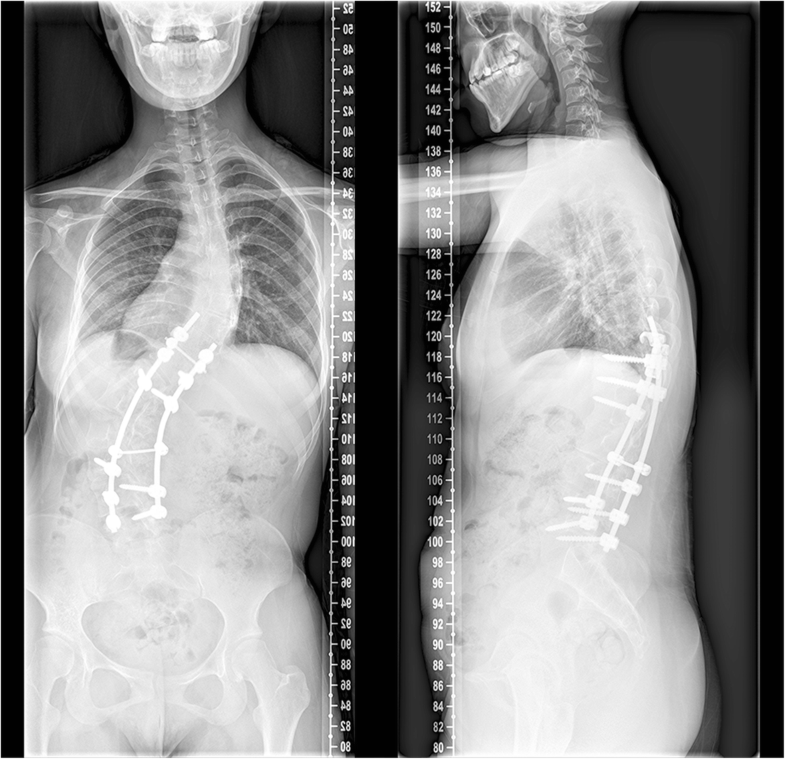

Kyphoscoliosis complications image This image demonstrates Kyphoscoliosis complications.